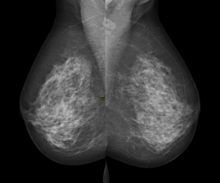

Digital mammography

Digital mammography is a specialized form of mammography that uses digital receptors and computers instead of x-ray film to help examine breast tissue for breast cancer.[1] The electrical signals can be read on computer screens, permitting more manipulation of images to theoretically allow radiologists to more clearly view the results.[1][2] Digital mammography may be "spot view", for breast biopsy,[3] or "full field" (FFDM) for screening.[1]

Digital mammography is also utilized in stereotactic biopsy. Breast biopsy may also be performed using a different modality, such as ultrasound or magnetic resonance imaging (MRI).

While radiologists[4] had hoped for more marked improvement, the effectiveness of digital mammography was found comparable to traditional x-ray methods in 2004, though there may be reduced radiation with the technique and it may lead to fewer retests.[1] Specifically, it performs no better than film for post-menopausal women, who represent more than three-quarters of women with breast cancer.[5]